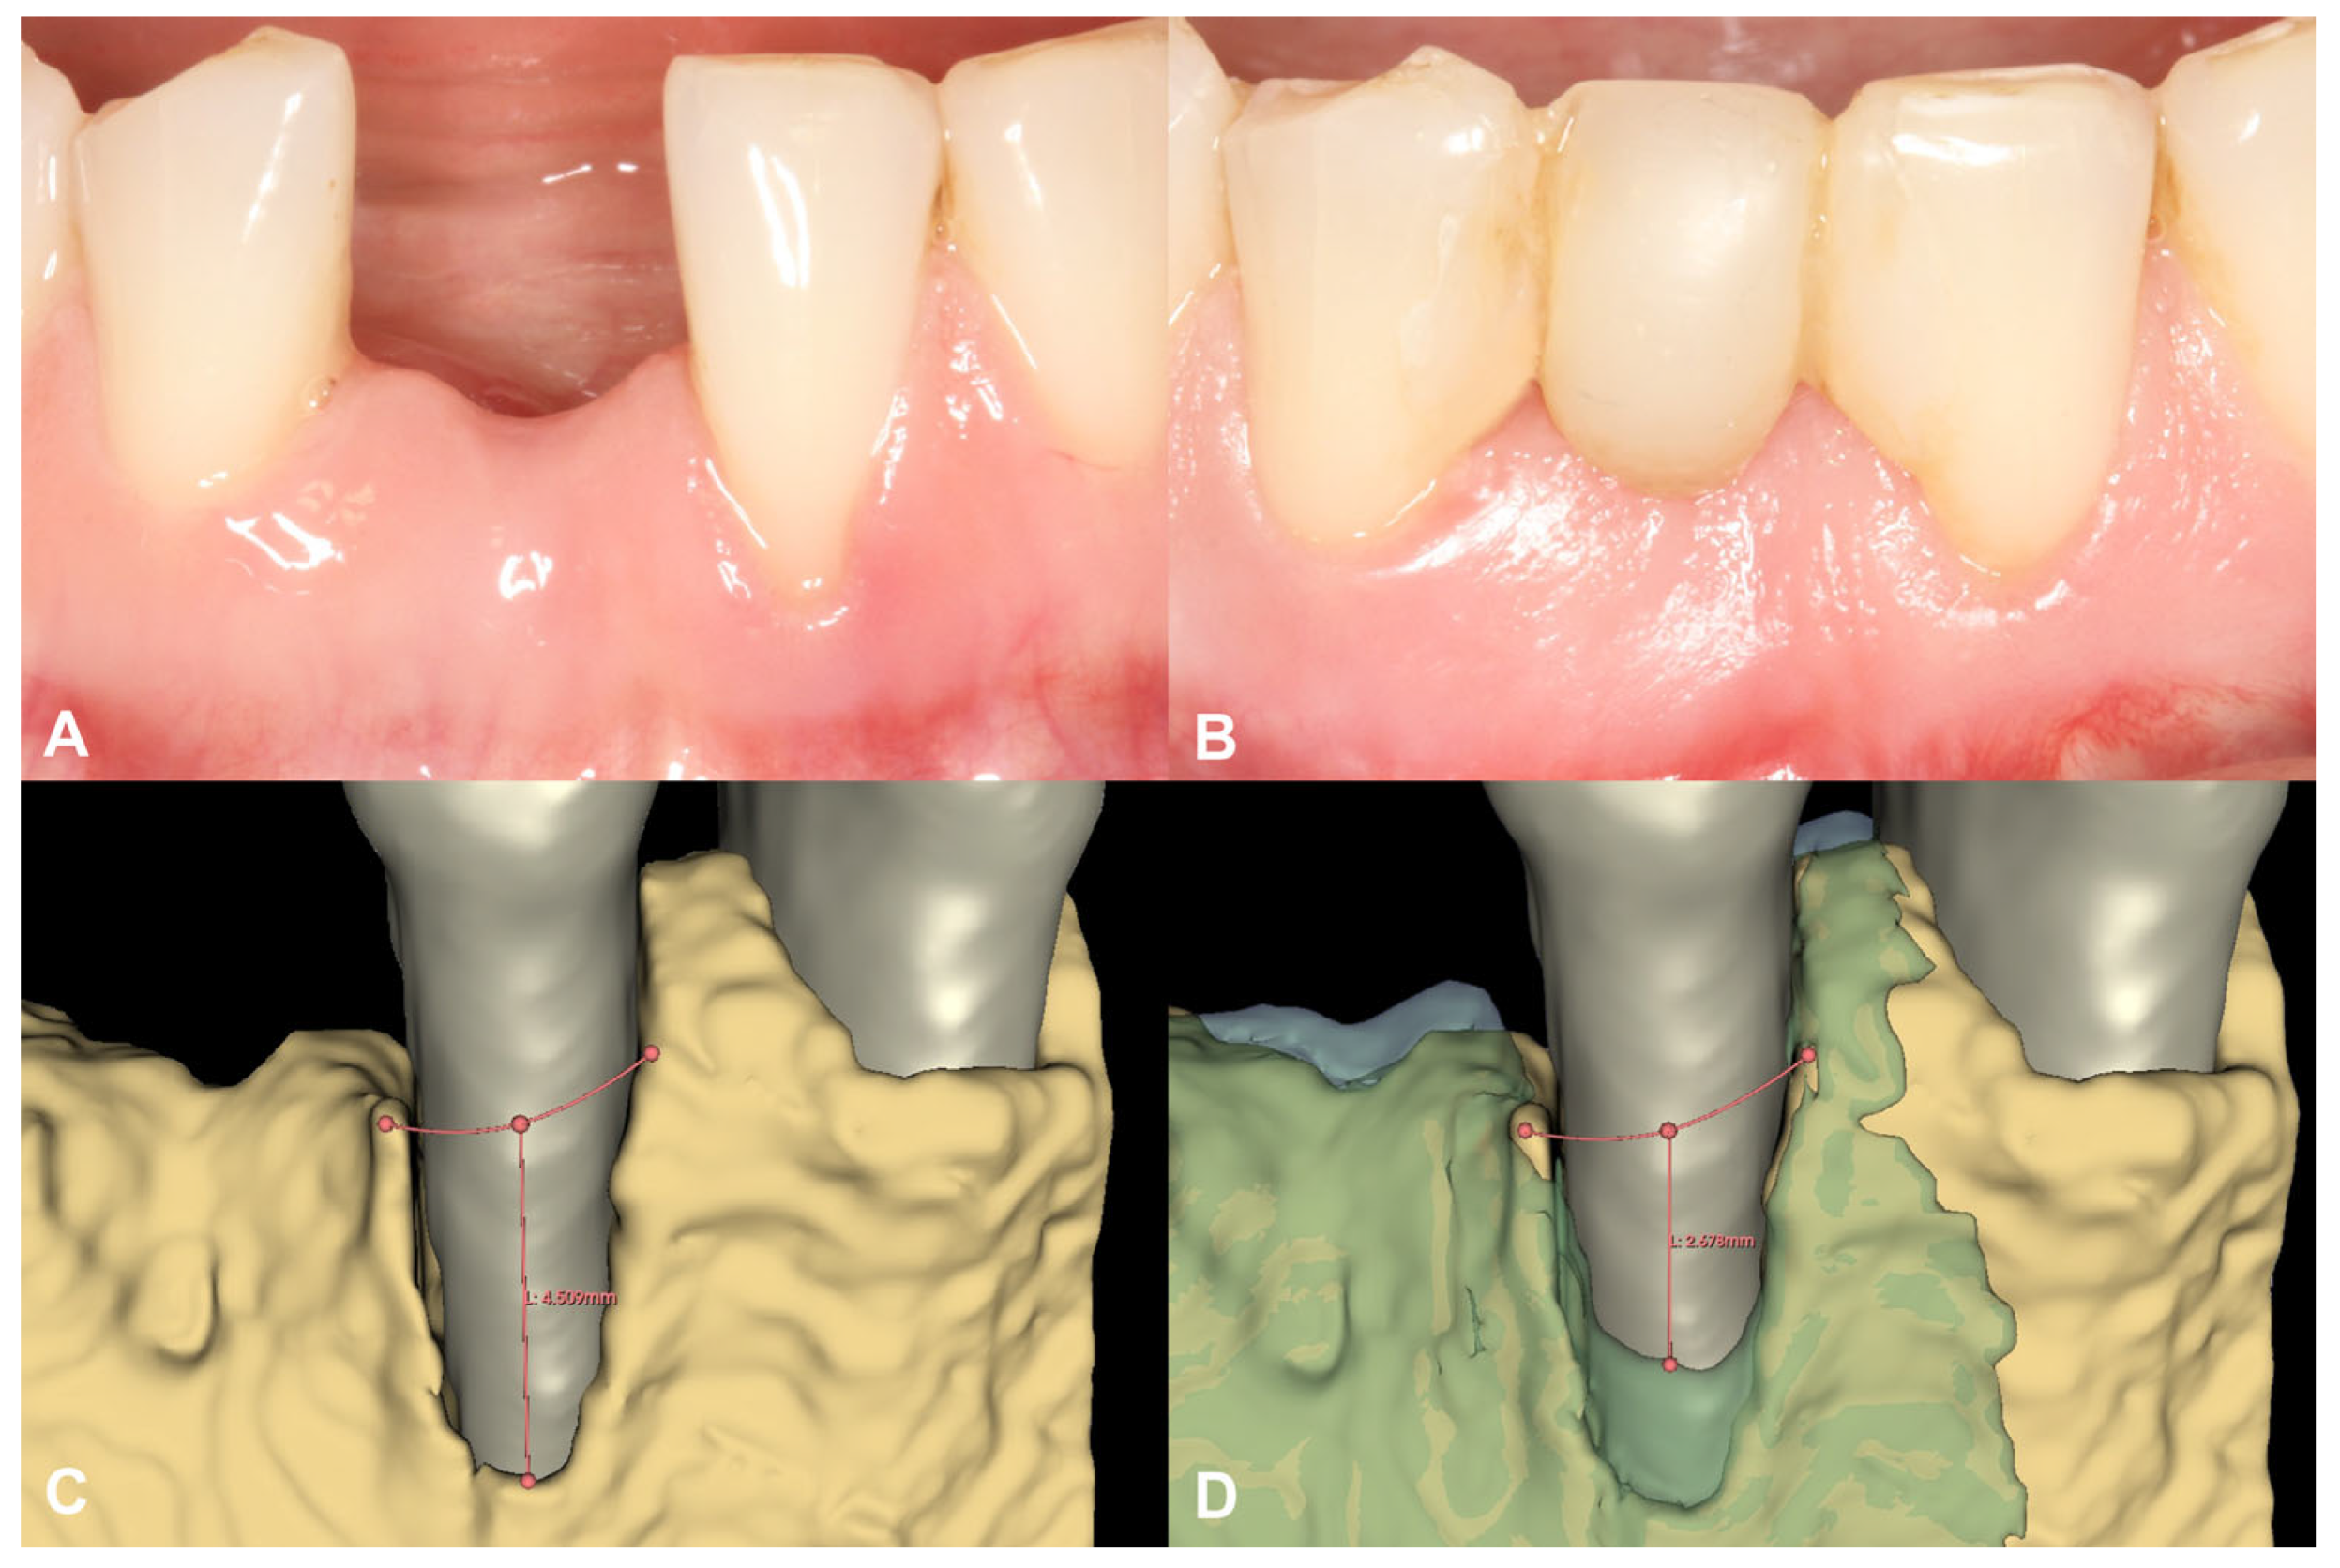

3.2. Case #2

3.2.1. Baseline Clinical Situation

3.2.2. Short-Term Volumetric Hard Tissue Gain and Long-Term Follow-Up